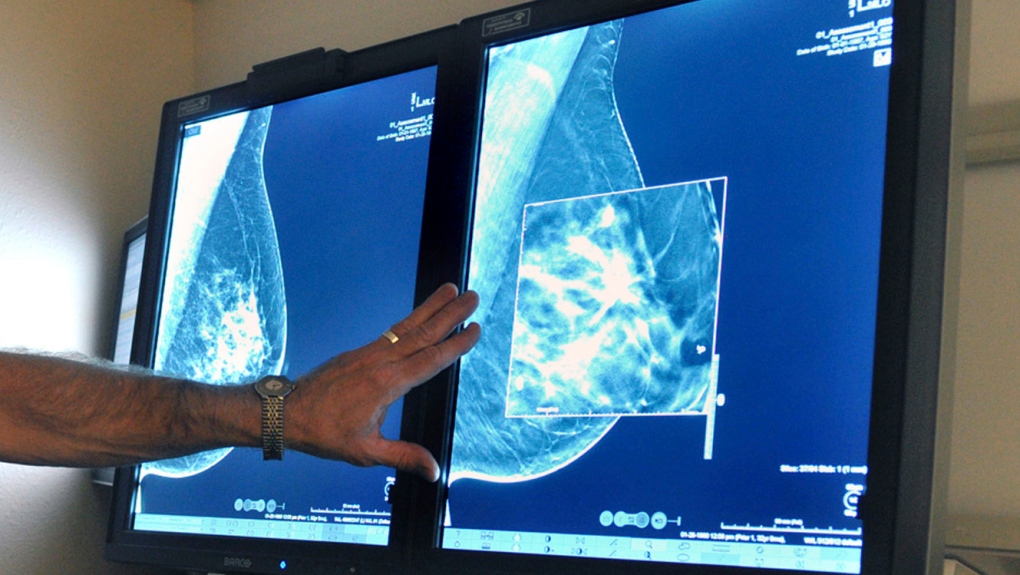

Një studim i ri tregon se pas 10 vitesh ekzaminimi vjetor të kancerit duke përdorur mamografinë 3D, gati gjysma e pacientëve të testuar përjetuan një mamografi false që tregonte sikur ishin pozitivë.

I publikuar të premten në JAMA Netëork Open, studimi vëzhgues sugjeron se ndërsa më shumë informacion mund të mblidhet duke përdorur mamografinë 3D, përdorimi i saj e ul shumë pak mundësinë e një rezultati të rremë pozitiv kur krahasohet me mamografinë standarde 2D.

Një rezultat pozitiv i rremë ndodh kur një mamografie i jepet një vlerësim pozitiv për shkak të një lloj anormaliteti që ka nevojë për më shumë punë diagnostikuese, duke përfshirë imazhe dhe testime të mëtejshme, por në fund të fundit nuk ka diagnozë të kancerit të gjirit.

“Pavarësisht përfitimit të rëndësishëm të mamografisë depistuese në reduktimin e vdekshmërisë nga kanceri i gjirit, ajo mund të çojë në procedura shtesë imazherike dhe biopsie, kosto financiare dhe oportune dhe ankth të pacientit,” Diana Miglioretti, profesoreshë e biostatistikës në UC Davis dhe autore e studimit. , thuhet në një komunikatë për shtyp të premten.